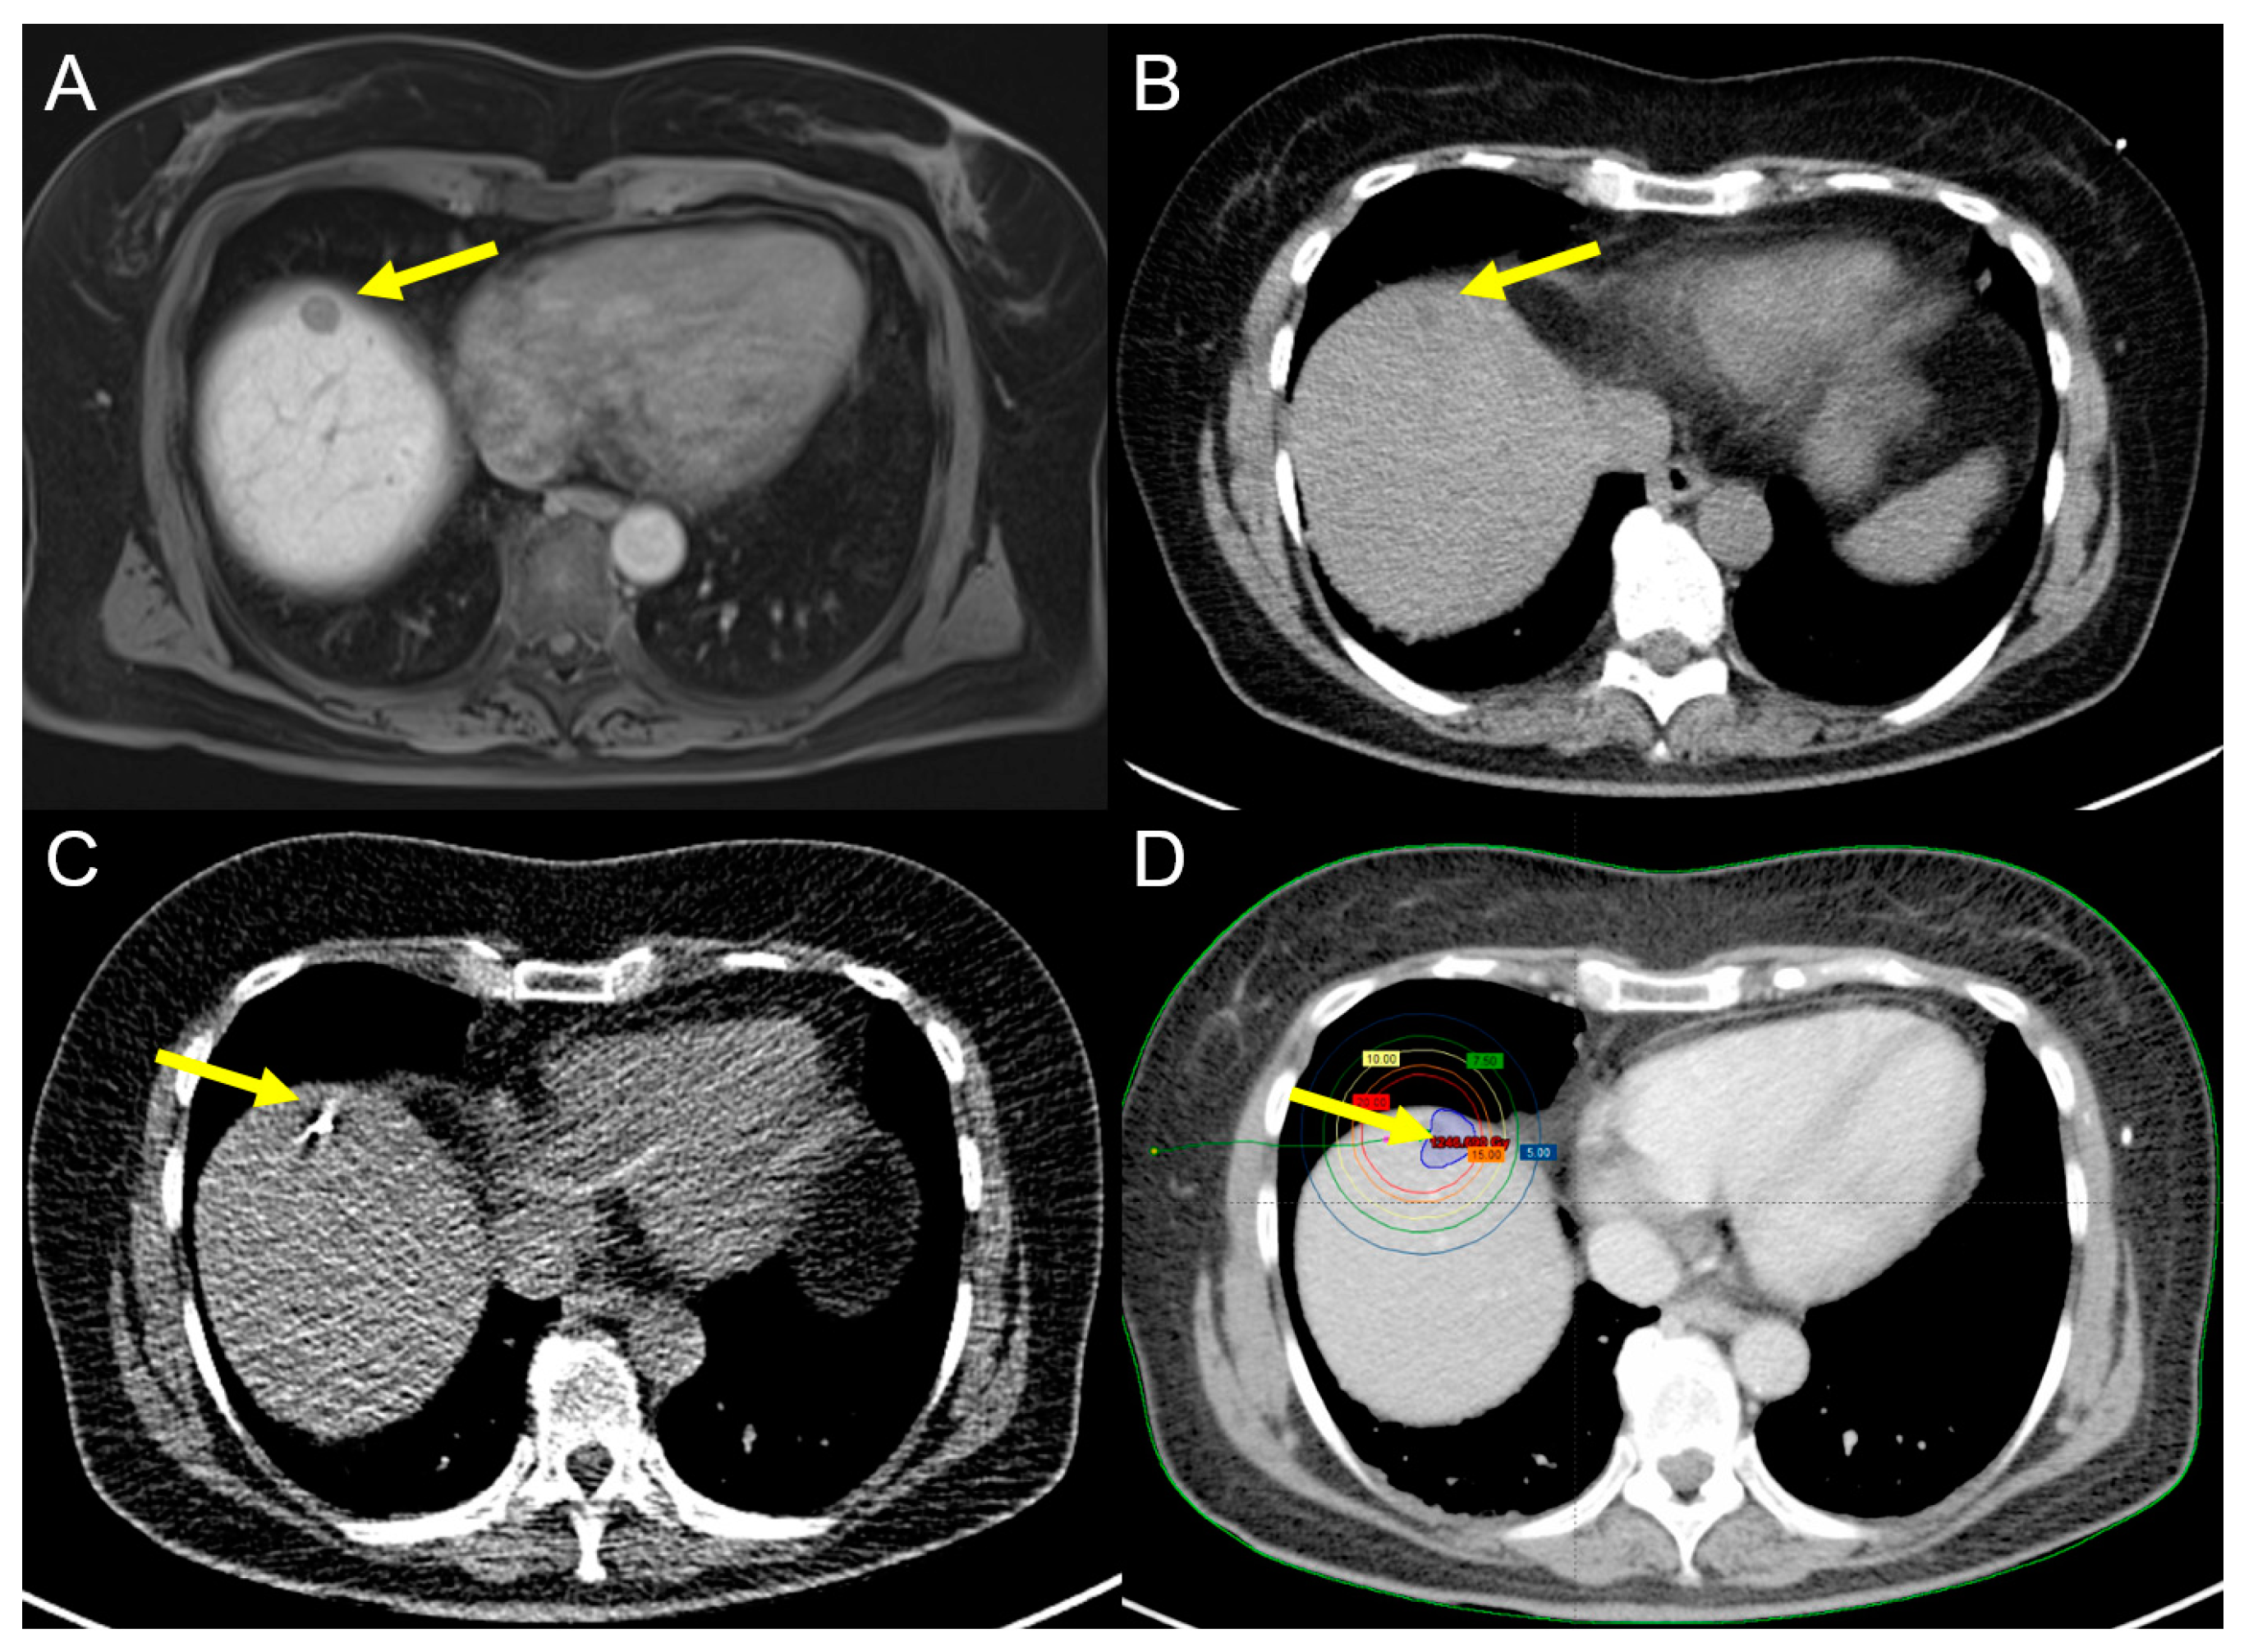

2.1.1. Radiofrequency Ablation (RFA)

2.1.2. Microwave Ablation (MWA)

2.2.1. Computed Tomography High-Dose-Rate Brachytherapy (CT-HDRBT)

2.2.2. Irreversible Electroporation (IRE)